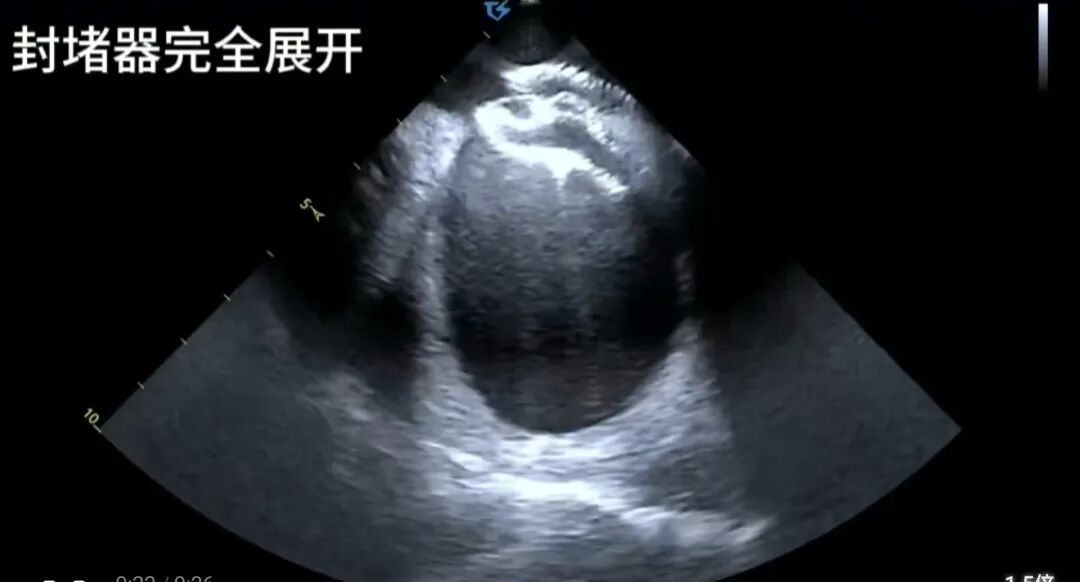

微创“修心”:心腔内超声引领下的精准封堵

经过周密的术前准备,电生理团队王睿、郭敏主任医师如期进行手术,术前先进行右心导管检查,结果令人振奋:患者术中实测肺动脉压仅为28mmHg,且肺血管阻力并未显著增高,这意味着其肺动脉高压在很大程度上是可逆的,并非手术的绝对“拦路虎”。这一精准判断,彻底推翻了此前“无法手术”的结论,为微创介入治疗奠定了坚实基础。本次手术全程在心腔内超声(ICE) 的实时精确引导下进行,与传统的X射线透视引导的不同之处在以下几个方面:

操作更精准:在超声的直视下,导丝穿越缺损、输送鞘管建立轨道、封堵器精准释放在房间隔缺损处,每一步都精准无误。

评估更即时:释放封堵器后,立即通过超声评估其位置是否稳固、是否影响周围瓣膜功能、残余分流情况,确保了手术的即时成功率与安全性。

最终,一枚合适的封堵器被完美释放,术后超声提示封堵器位置固定良好,无残余分流,不影响心脏内正常血流,手术取得圆满成功。